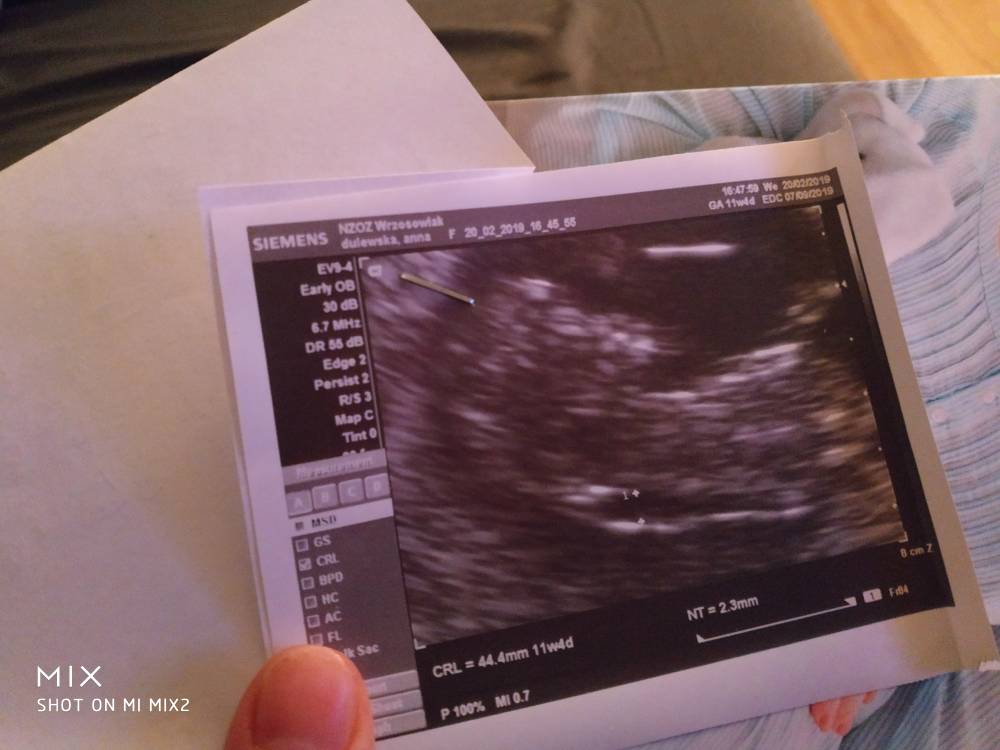

A to mój niewyraźny dzidziolek [emoji23][emoji7]

IMG_20190220_211209.jpeg